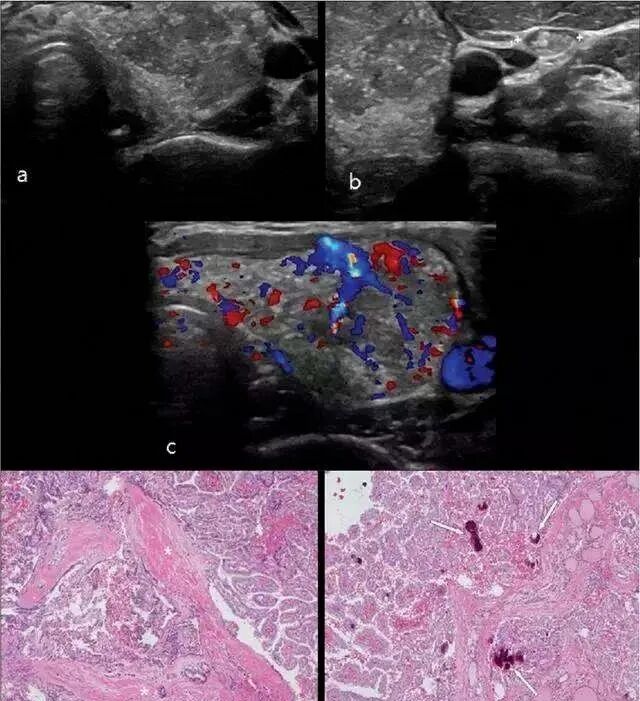

科学研究表明,人体的甲状腺中存在成体干细胞。通过对人体甲状腺成体细胞进行分离、培养以及诱导分化,科研人员发现这些成体干细胞在体外能够分化生成具备一定生物学功能的甲状腺细胞。这些研究为甲状腺干细胞奠定理论基础。

2011年,中国研究人员在《中国组织工程研究》杂志中证实了脐带间充质干细胞可诱导培养为甲状腺细胞,他们建立了大鼠间充质干细胞体外诱导为甲状腺细胞的方法,采用了密度梯度法分离间充质干细胞,用促甲状腺素和胰岛素诱导,最后通过形态学以及生物学证实了诱导分化生成的细胞中含有甲状腺细胞